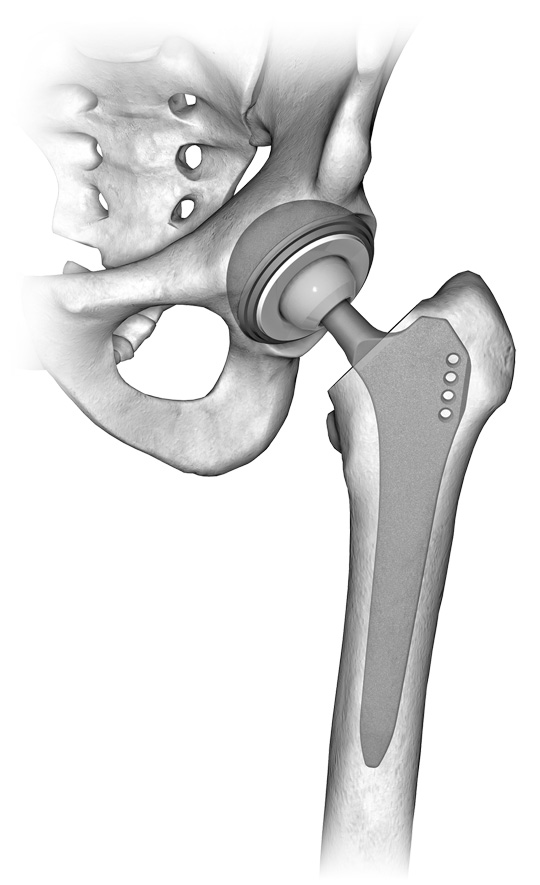

Una protesi articolare è composta da uno stelo femorale di solito in titanio, una coppa acetabolare anch'essa in titanio. La testa femorale e l'inlay sono disponibli in metallo, polietilene oppure ceramica.

A seconda della qualità ossea le componenti possono essere cementate o non.